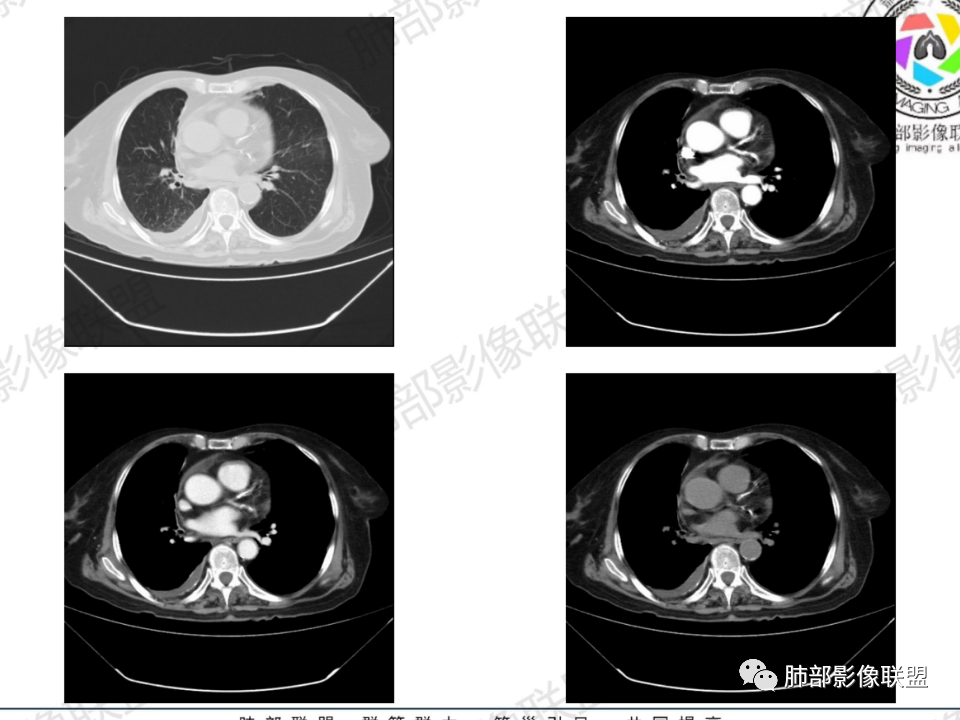

那个人:老年女性,亚急性病程,咳嗽发热。有垂体前叶功能减退,目前激素替代治疗,长期激素,量小,不知道累积量,没有目前激素水平指标。既往有淋巴结结核病史。肿瘤标记物Ca125升高。血沉升高,C反应蛋白轻度异常。影像,右肺上叶靠近肺门团块影,右肺门淋巴结钙化肿大,支气管狭窄,局部增厚,团块影外朝内改变,强化明显,血管破坏不明显,有粘液。和纵隔胸膜分界清楚,周围肺组织有斑片渗出影,右侧胸腔积液,考虑炎性?结核?支气管镜检查除外恶性飞鹰行动:老年患者,影像表现 右肺上叶占位性病变,边界清楚,有分叶征,内见细小钙化,右肺上叶支气管截断,增强病灶不均匀强化,病灶内有条状坏死区(扩张的支气管?),纵膈内未见增大淋巴结,考虑炎性病变,结核可能。一切∮随缘:右肺上叶实性肿块形态不规则,呈三角形,边缘分叶,边界伴有磨玻璃影,近段支气管未见明显显示,可能堵塞,病变平扫密度均匀,增强后可见低密度坏死无强化,周围略强化,右肺下叶散在结节。心包积液,及右侧胸腔积液,临床:有低热,低蛋白血症,肿瘤标记物高,考虑恶性:腺癌,神经内分泌癌(强化偏弱了),淋巴瘤,鉴别:结核红星:老年女性患者右肺上叶,肺门上区 分叶状肿块 ,右肺上叶支气管显示不清,增强扫描肿块,中等程度强化可见小斑片状坏死区,病灶内部可见斑点状钙化灶,病灶周围可见斑片状及小斑点状影,纵膈淋巴结增大,其他区域,胸膜下可见斑点状钙化。考虑肉芽肿性病变,结核的可能性大。老年患者最排除肿瘤性病变腺癌。土娃:右上肺不规则肿块影,边缘分叶,边界磨玻璃影欠清,病灶分叉状,内见点状钙化影及坏死灶,支气管堵塞,病灶增强强化不明显。考虑瘤样结核,鉴别淋巴瘤。张小兵:老年女性,亚急性病程,右肺上叶见不规则肿块,边缘平直凹陷为主,周围GGO边界不清,内见点状钙化及坏死灶,增强持续性渐进强化,右侧少量胸腔积液,双肺门及纵隔肿大淋巴结伴钙化,综合考虑慢性炎症。saf:老年患者,影像表现 右肺上叶占位性病变,边界清楚,有分叶征,增强病灶明显不均匀强化,纵膈内未见增大淋巴结,考虑炎性病变,结核可能。小兜:老年女性,咳嗽喘息一月,发热三天,肿瘤标志物升高,长期激素替代治疗。CT示右肺上叶近肺门不规则实变影,周围伴磨玻璃影,增强持续性渐进强化,内部血管破坏不厉害,内部可见多发条形低密度灶,右侧胸腔可见少量积液,双肺门及纵隔可见钙化淋巴结,考虑为炎性病变,结核可能玫:女,79咳嗽,喘息一月,发热三天入院,右肺上叶不规则形软组织密度肿块影,边界清晰,边缘见分叶及细短毛刺,病灶内见点状钙化影及稍低密度区,病灶边缘呈磨玻璃样改变,增强扫描,病灶呈不均匀性强化,考虑炎性病变,鉴别鳞癌。大雄:老年女性,既往诊断淋巴结结核,提示已治愈,近2年服用激素,诱导结核复燃→发热;纵隔肺门淋巴结肿大钙化,压迫支气管,右肺上中下叶支气管均狭窄→喘息咳嗽;尖段支气管受累闭塞→肺不张、支气管粘液栓;累及胸膜,结核性胸膜炎并胸水→右侧胸痛;实验室,血沉快,CA125高,低蛋白,符合;下一步,支气管镜尖段支气管刷检抗酸染色周太狼:老年女性,亚急性病程,肿瘤标志物升高。CT示右肺上叶尖段不规则肿块影,有分叶、收缩,周围伴磨玻璃影,增强渐进强化,内部可见多发条形低密度灶,右侧胸腔及心包少量积液,纵隔内淋巴结稍增大。倾向于恶性病变,肺癌伴阻塞性炎变可能。丽:老年女性,右肺上叶不规则软组织肿块,边缘清晰,内密度不均,可见点状钙化及粘液栓,周围可见片状高密度影,增强后均匀强化,内多发低密度,纵膈多发钙化淋巴结,考虑结核可能大,建议结合支气管镜检查除外肿瘤宇宙:右胸廓缩小,右肺上叶团块影及不张,平直边,周围磨玻璃影,纤细胸膜牵拉,上叶尖段支气管堵塞,明显延迟强化,可见支气管粘液栓,两肺门钙化淋巴结,右侧胸水,考性炎性肉芽肿,鉴别腺癌王秀仙:右肺上叶肺门区肿块,上叶支气管开口阻塞,形态不规则,密度不均,内可见支气管粘液栓及多发小灶性坏死,周围磨玻璃影边缘模糊,渐进强化,右侧胸腔积液、胸膜钙化,考虑炎性肉芽肿性病变,慢性炎症。鉴别鳞癌,结核。刘丹:老年女性,右肺上叶肿块伴钙化,右肺上叶支气管截断,增强后均匀强化,周边可见点片状模糊影,右侧胸腔积液,右肺门淋巴结增大,考虑占位并阻塞性炎症,肿瘤?结核?建议纤支镜检查。小飞:右肺上叶纵隔旁软组织肿块,边缘深分叶、长毛刺及毛刷样短毛刺,边缘磨玻璃影,磨玻璃边界模糊,支气管截断,平扫密度不均,可见点状钙化,增强不均匀明显强化,心影增大,心包积液,右侧胸腔积液,考虑恶性肿瘤,腺癌?秦化君:右肺上叶不规则分叶软组织密度肿块,边缘清晰,胸膜牵拉,周围花花草草,上叶尖段支气管阻塞,内可见点状钙化,增强后密度不均可见支气管粘液栓及坏死区,内见血管分枝。中间段及中叶,下叶支气管狭窄,壁见钙化。右肺门淋巴结肿大,右侧胸腔积液,心包粘连肥厚。考虑1右上肺恶性病变,鳞癌?2右肺多叶段支气管狭窄,考虑支气管内膜结核?3胸腔积液及肺门淋巴结肿大,转移?风儿:老年女性,右肺上叶肿块,形态不规则,外围大内带小,边缘分叶膨隆平直及毛糙,密度不均,内见支气管粘液栓及多发小灶性坏死,坏死边缘清晰 ,渐进强化,上叶尖段支气管阻塞,叶支气管壁有局限性增厚,邻近胸膜腔微积液;纵隔及双肺门淋巴结肿大,部分钙化,右侧胸腔积液、心包积液、胸膜钙化,考虑炎性,肉芽肿性结核可能性大。鉴别鳞癌,女性及血供均不支持;腺癌,坏死边界太清晰。流心明智:老年女性,79岁,咳嗽、气短1月,发热3天。胸CT:右肺上叶见不规则肿块,边缘有膨隆、有平直凹陷,周围GGO边界不清,病灶内见点状钙化、粘液栓,尖段支气管未见,增强持续性渐进强化,右侧少量胸腔积液,双肺门及纵隔肿大淋巴结伴钙化,肺动脉增粗。考虑:右上叶尖段堵塞并慢性炎症,支气管TB并结石?鉴别Ca

临床信息:老年女性,亚急性病程,咳嗽发热。有激素使用史。既往有淋巴结结核病史。肿瘤标记物Ca125升高。血沉升高,C反应蛋白轻度异常。 影像所见:右侧胸廓相对狭小,右肺上叶不规则团块影贴附纵隔旁,轻度分叶,整体密度较均匀,偶见钙点。

相应上叶尖端及前段支气管开口未能追踪(阻塞),开口处见钙化。病灶渐进性强化,并衬托出较完整尖段及前段含液支气管影。支气管开口区域未见异常高密度强化(如类癌等)及相对乏血供区(如鳞癌)。病灶区未见液化坏死。右上纵隔及胸廓入口区未见病灶胸膜外突破(栽赃)。

右肺上叶后段等区域散在片状影,边界不清(提示渗出性病灶)。

纵隔及双肺门见钙化淋巴结。心包积液,右侧胸腔积液(提示存在活动新病灶)。双侧胸膜下见多发斑点状钙化,胸廓变形(提示存在结核基础病变可能)。 诊断意见:综上,右肺上叶块状影更符合继发性肺结核。 最后小结:既往诊断淋巴结结核,提示已治愈。近2年服用激素,可疑诱导结核复燃,也可引起发热。纵隔肺门淋巴结肿大钙化,压迫支气管,右肺上中下叶支气管均狭窄,所以引起喘息咳嗽。尖段支气管受累闭塞,导致肺不张、支气管粘液栓,出现条状无强化区。病变累及胸膜,导致结核性胸膜炎并胸水,引起右侧胸痛。实验室检查血沉快,CA125高,低蛋白,均符合结核。下一步,建议支气管镜尖段支气管刷检并抗酸染色。(本段摘自於雄老师精彩发言)